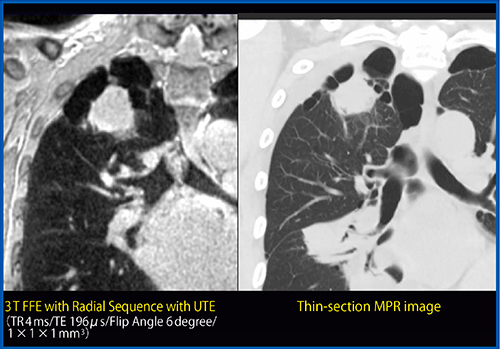

Pulmonary MR imaging with ultra-short TE(UTE-MRI)は,元来,T2*値の極端に短い生体内の構造におけるMRIの手法として開発され,主に骨軟部領域に応用されてきた。本手法を肺末梢のT2*値解析に応用することによって肺局所のT2*mapを作成することが可能であり,肺気腫や膠原病に伴う肺病変などの間質性肺炎の重症度評価を可能としている26)〜28)。そして,さらに近年の報告では,薄層CTと同様の画像を取得することが可能であるとの報告もある29),30)。われわれも本手法を開発し,臨床応用することに成功した(図5)。今後はさらなる臨床応用研究を行うとともに,東芝メディカルシステムズ社とともにさらなる画質改善を行い,本手法の臨床における有用性に関しても評価した上で,薄層CTとの使い分けなどを含めて,その臨床適応などに関しても明らかにしたいと考える。

図5 72歳,男性,肺扁平上皮癌

UTE-MRIおよび薄層CTにおいて右肺尖部の肺扁平上皮癌および周囲のブラや肺気腫は同様に描出されており,肺末梢の血管や気管支などの末梢構造の描出も同等であるので,今後の臨床応用が期待される。